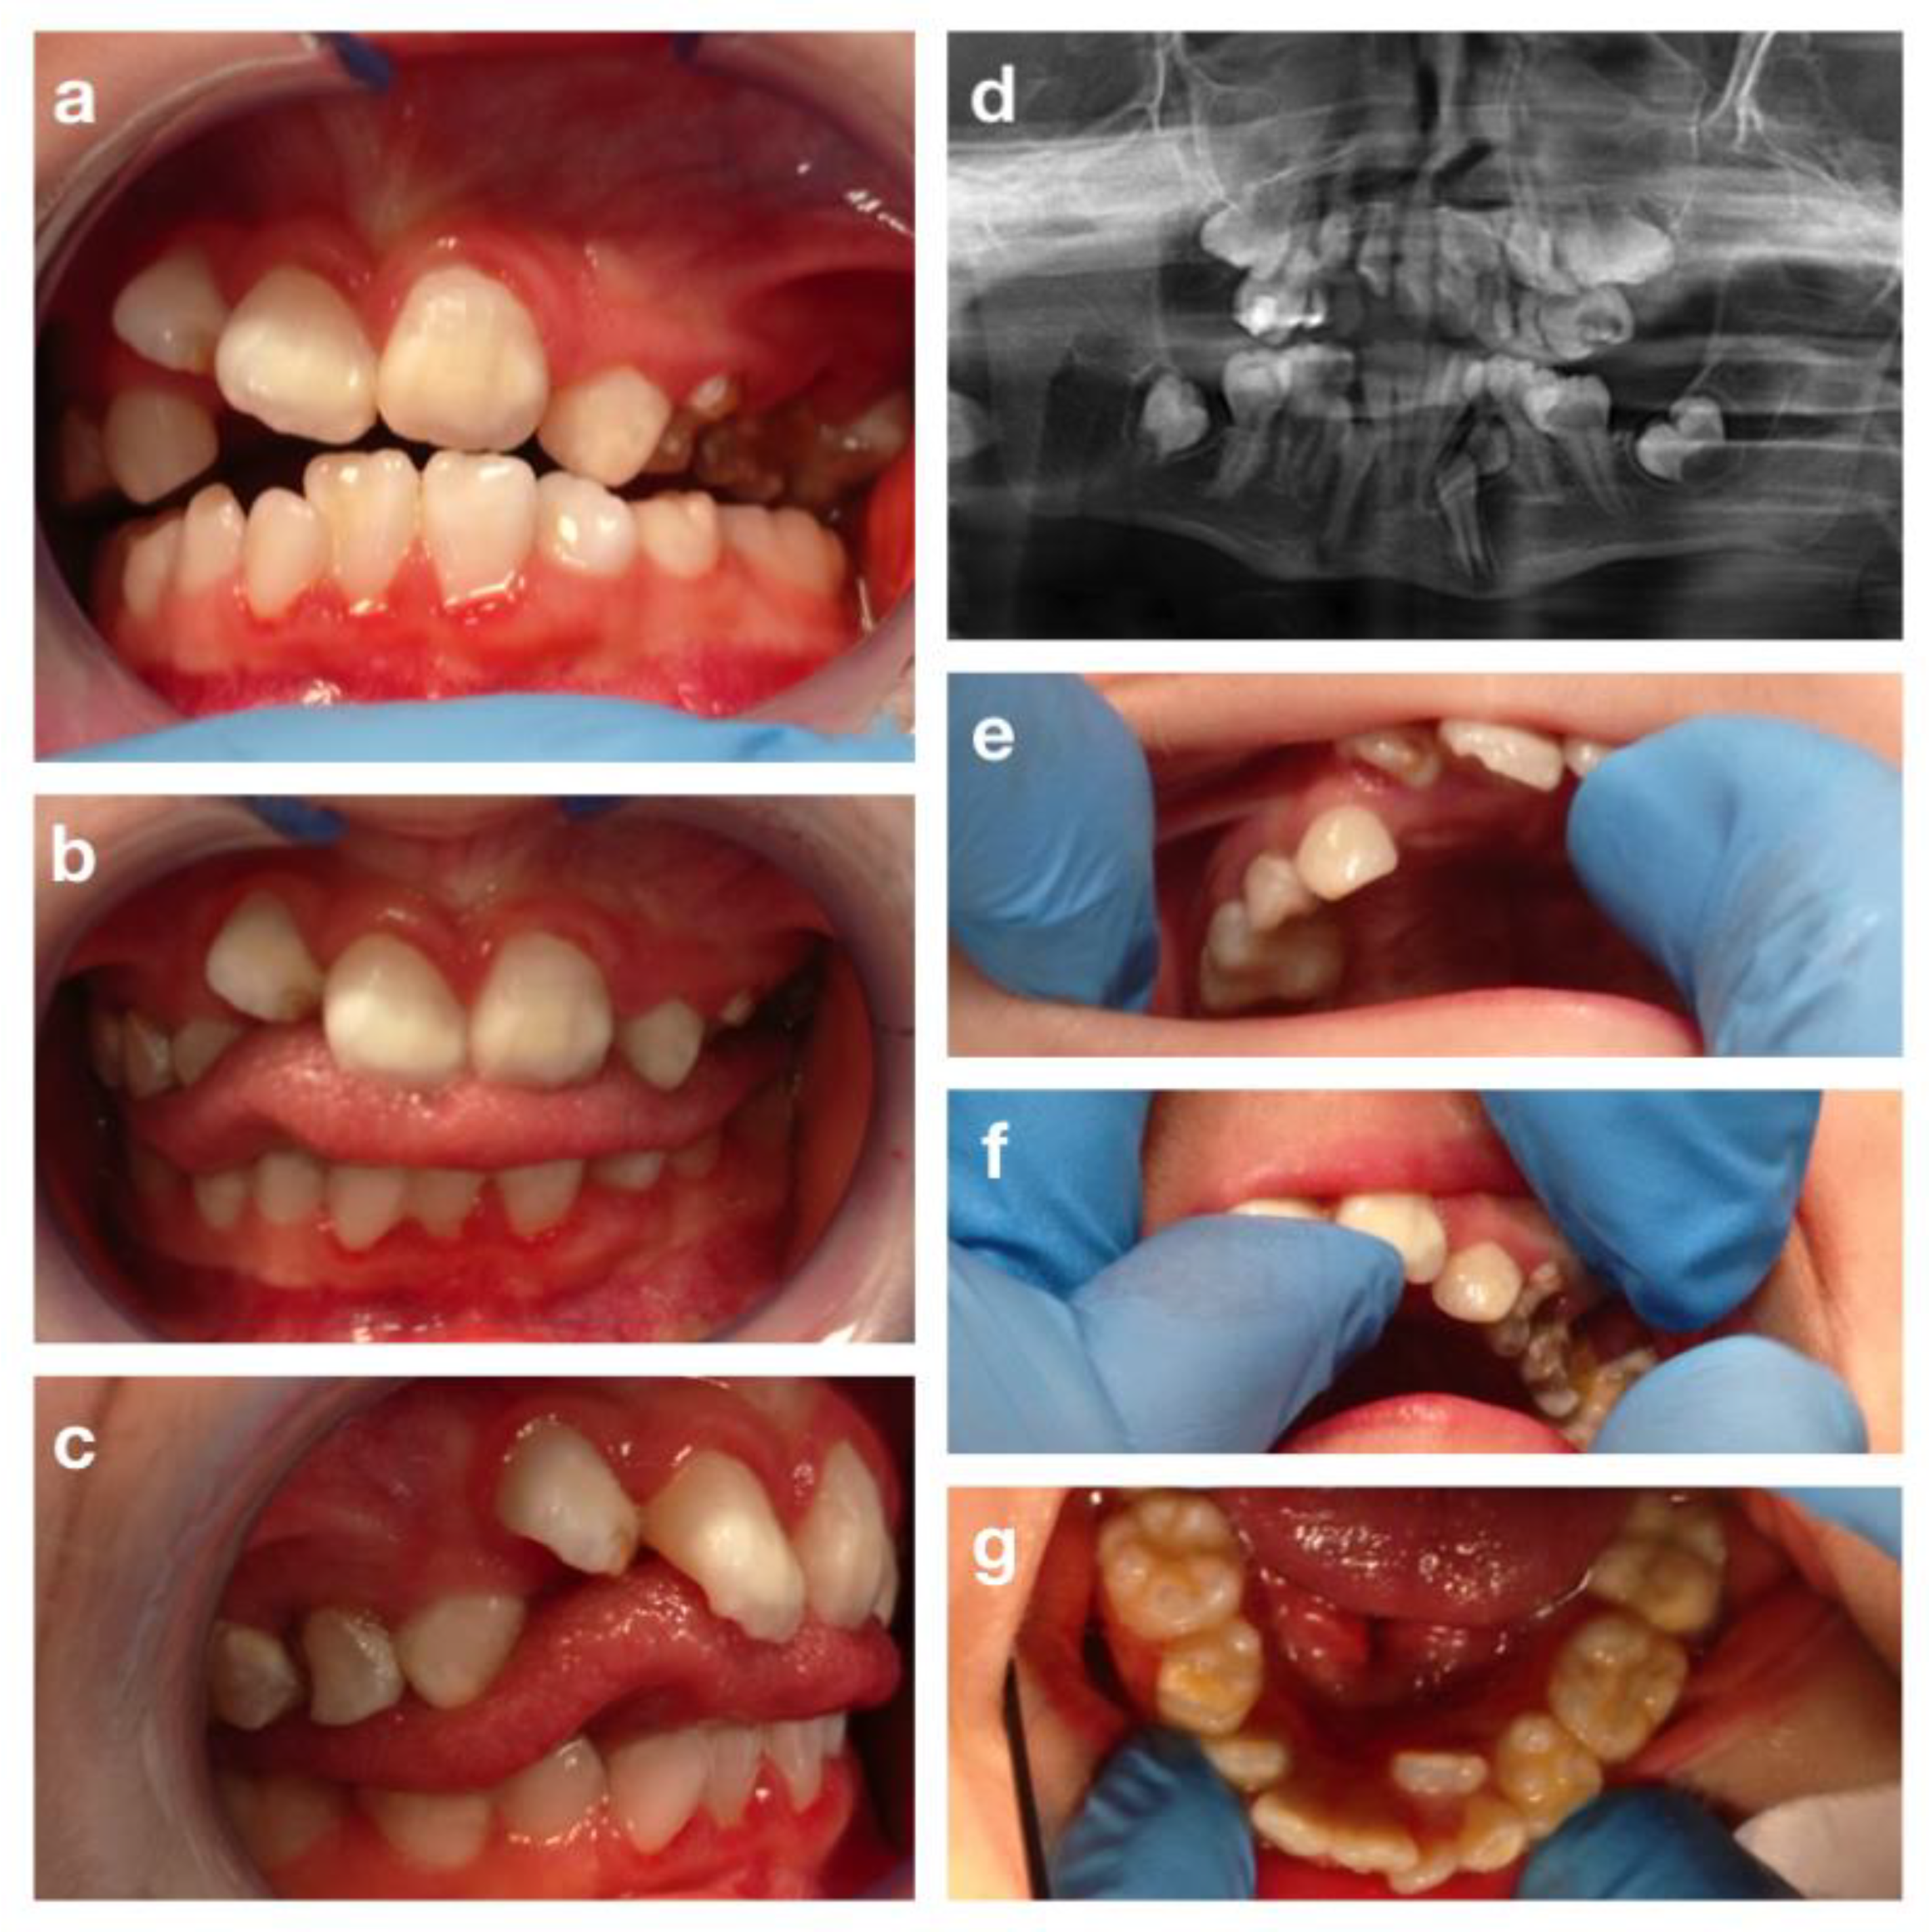

3.3. CHARGE Syndrome

3.4. The Cornelia De Lange Syndrome